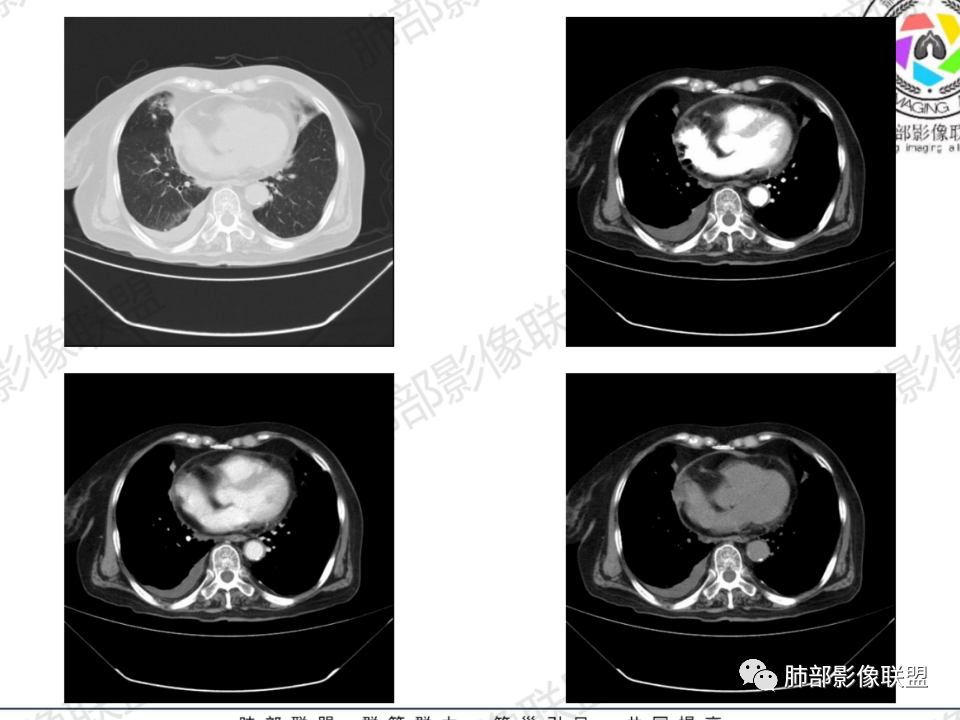

临床信息:老年女性,亚急性病程,咳嗽发热。有激素使用史。既往有淋巴结结核病史。肿瘤标记物Ca125升高。血沉升高,C反应蛋白轻度异常。 影像所见:右侧胸廓相对狭小,右肺上叶不规则团块影贴附纵隔旁,轻度分叶,整体密度较均匀,偶见钙点。

相应上叶尖端及前段支气管开口未能追踪(阻塞),开口处见钙化。病灶渐进性强化,并衬托出较完整尖段及前段含液支气管影。支气管开口区域未见异常高密度强化(如类癌等)及相对乏血供区(如鳞癌)。病灶区未见液化坏死。右上纵隔及胸廓入口区未见病灶胸膜外突破(栽赃)。

右肺上叶后段等区域散在片状影,边界不清(提示渗出性病灶)。

纵隔及双肺门见钙化淋巴结。心包积液,右侧胸腔积液(提示存在活动新病灶)。双侧胸膜下见多发斑点状钙化,胸廓变形(提示存在结核基础病变可能)。 诊断意见:综上,右肺上叶块状影更符合继发性肺结核。 最后小结:既往诊断淋巴结结核,提示已治愈。近2年服用激素,可疑诱导结核复燃,也可引起发热。纵隔肺门淋巴结肿大钙化,压迫支气管,右肺上中下叶支气管均狭窄,所以引起喘息咳嗽。尖段支气管受累闭塞,导致肺不张、支气管粘液栓,出现条状无强化区。病变累及胸膜,导致结核性胸膜炎并胸水,引起右侧胸痛。实验室检查血沉快,CA125高,低蛋白,均符合结核。下一步,建议支气管镜尖段支气管刷检并抗酸染色。(本段摘自於雄老师精彩发言)